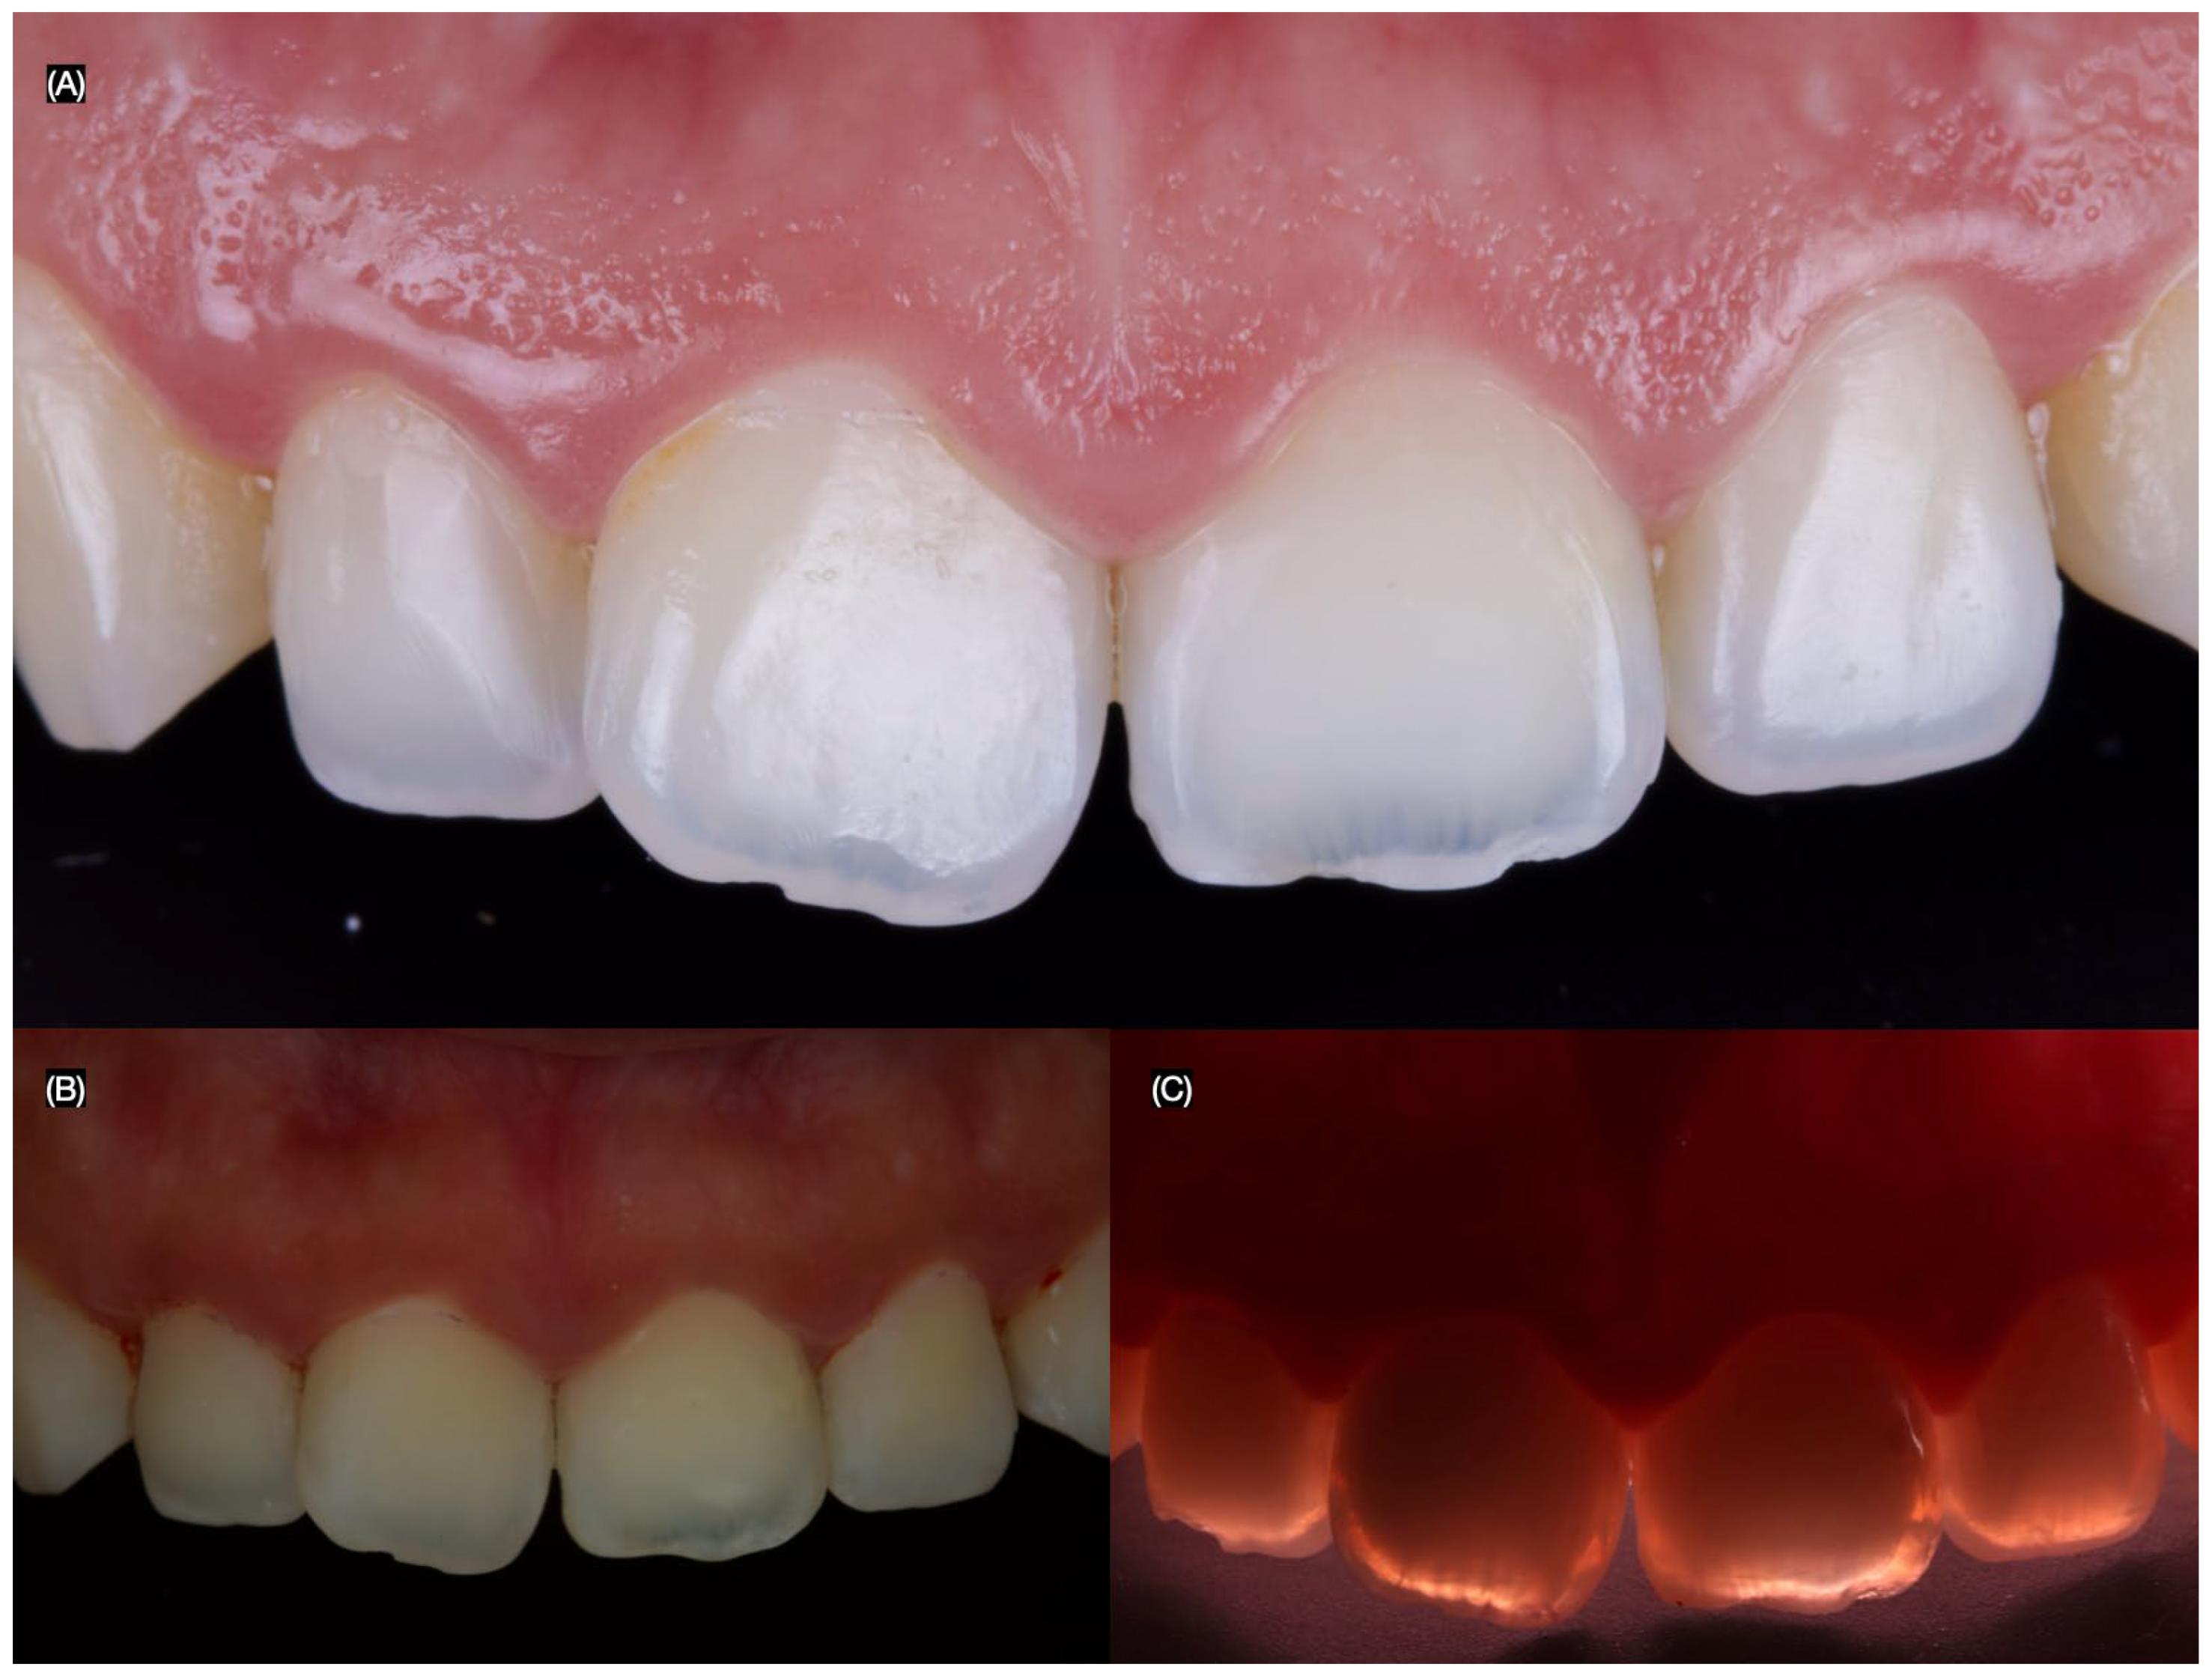

3.2. Results of the Case Study

4.5. Case Report